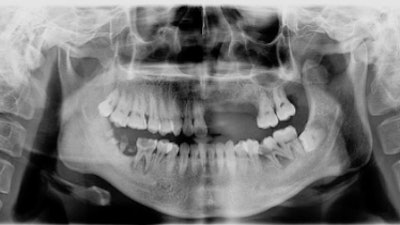

A panoramic radiograph taken during the man's first visit.